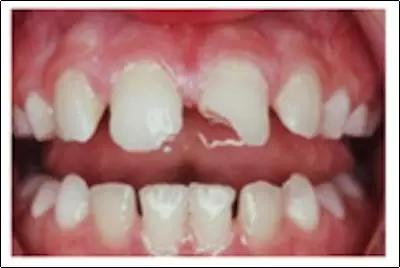

新年聚餐吃饭、喝酒是很多人的固定活动,但也有人为了打开酒瓶盖,用牙“咔嘭”一下,瓶盖没打开,牙裂了;吃菜时啃骨头,却无奈骨头太硬,骨头没咬碎,牙齿先折断了……

牙齿不是工具,虽然它足够硬,但请你把它当“瓷器”一样爱护吧。不然,等着你的结果可能是这样: